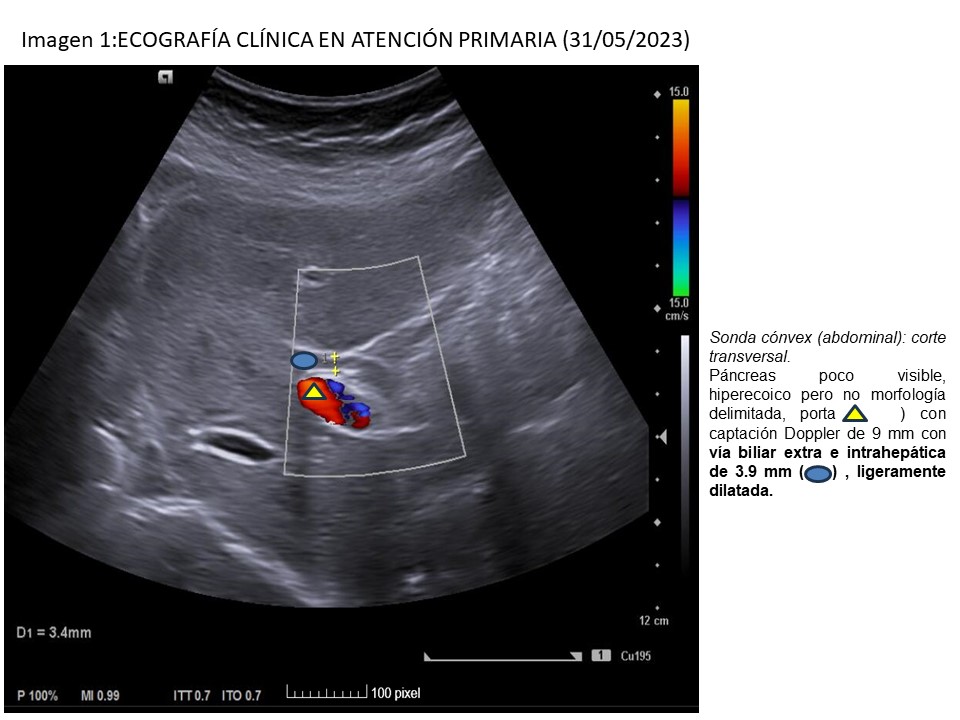

• Ecografía clínica-AP (31/05): páncreas poco visible, hiperecoico, no delimitado; porta de 9 mm con vía biliar ligeramente dilatada (3,9 mm), vesícula con barro biliar, paredes finas.